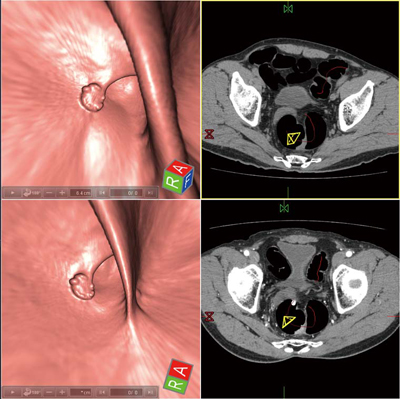

CT装置本体上での大腸解析を可能とする“コロンビューイングソフトウェア”は,大腸領域を抽出したフライスルー(仮想内視鏡像)や,フライスルーとMPR像のフュージョン画像,大腸を切り開いた360°展開画像(フィレビュー)とさまざまな表示が可能である。表示画面より病変部位を速やかに把握するとともに,病変周辺部分を細かく観察することができる。

さらに2体位を同時に表示できるため,腹臥位,仰臥位それぞれの画像を同一画面で比較しながら観察することも可能である。体位によって形態の変わる病変の観察ができ,残渣と病変の識別をサポートする。観察後には,キー画像を添付したレポート出力が可能である。

図1 コロンビューイングソフトウェアによる2体位比較表示